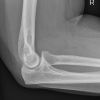

Radiusköpfchen; Greenspan

Radiusköpfchen:

Patient sitzt seitlich an der Breitseite des Tisches, Unterarm und Oberarm liegen in gleicher Höhe, Hand in Supination zum Körper. Sprich wenn es möglich ist die Hand so drehen, dass die Handinnenfläche nach oben zeigt.

Greenspan:

Pat. sitzt seitlich am Tisch. Oberarm, Ellenbogen und Unterarm liegen in gleicher Höhe, Ellenbogen 90° gebeugt, Handfläche liegt auf Kassette (auf Grund Bewegungseinschränkung oder Gips).

Im Winkel von 45° auf Mitte Ellenbogen in Richtung zum Radiusköpfchen (Daumenseite) medio-lateral.

Zielt im Winkel von 45° zum Unterarm auf das Radiusköpfchen – Radiusköpfchen liegt plattenfern. Aufnahme wird in umgekehrter Strahlenrichtung aufgenommen, als bei ausgestrecktem Arm.

Kann der Patient den Arm nicht voll durchstrecken, so kann diese Aufnahme auch in Beugung aufgenommen werden, dabei liegt der Unterarm auf (Hand in Supination) z.B. bei Gipskontrolle. -> Greenspan-Aufnahme. Diese Aufnahme sollte aber nur in Ausnahmefällen angewendet werde, da sie aus strahlenhygienischer Sicht durch die Strahlrichtung auf den Körper zu problematisch ist!

Orthograde, überlagerungsfreie Abbildung des Radiusköpfchen, freie Darstellung der Articulatio humero-ulnaris